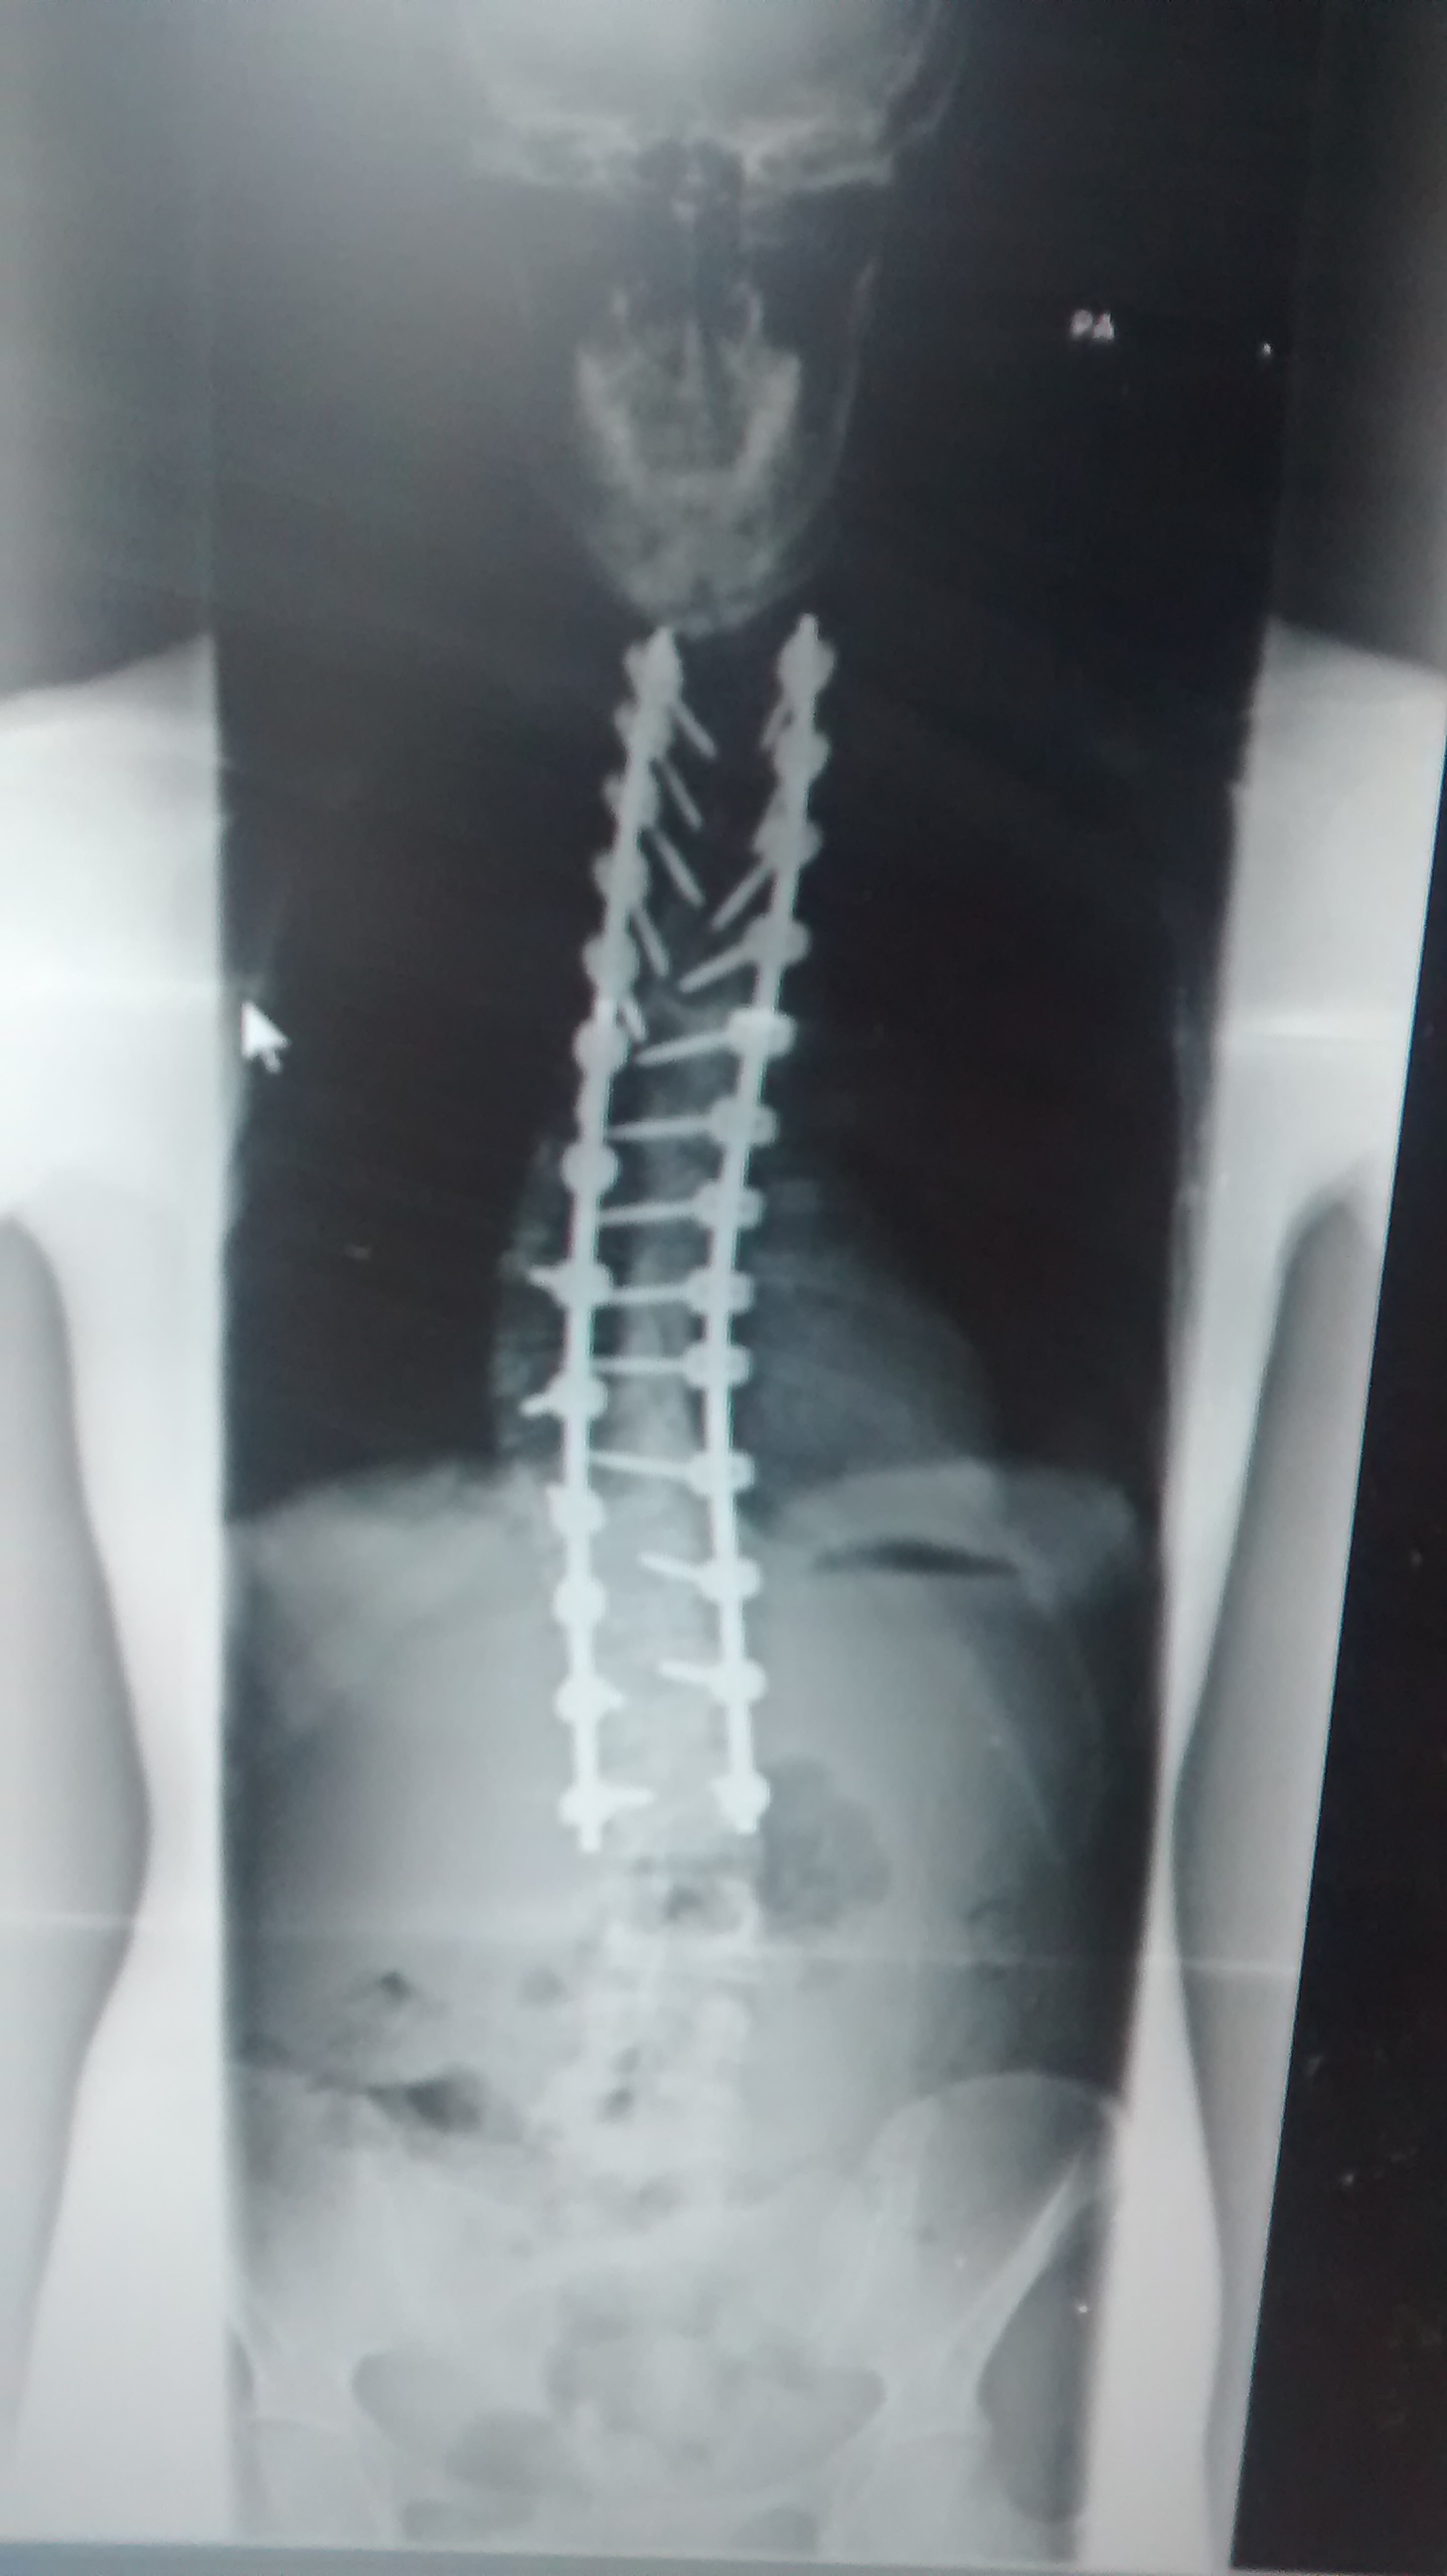

Lots of postures are accessible to those of us who’ve been through scoliosis surgery. A lot depends on where the fusion is. Back bends and twists are generally off the table but very gentle versions can be approached with awareness. Yoga is about exploring and listening to your body. Surgery doesn’t solve everything; there will still be muscular imbalances and the un-fused vertebrae have to do more work to compensate so they need looking after.

It’s best to focus on poses that maintain a neutral spine, which include many of the standing postures. Postures to strengthen the back muscles, develop core strength and lengthen the spine all help to maintain the health of a fused spine and encourage more fluid movement in the upper body.